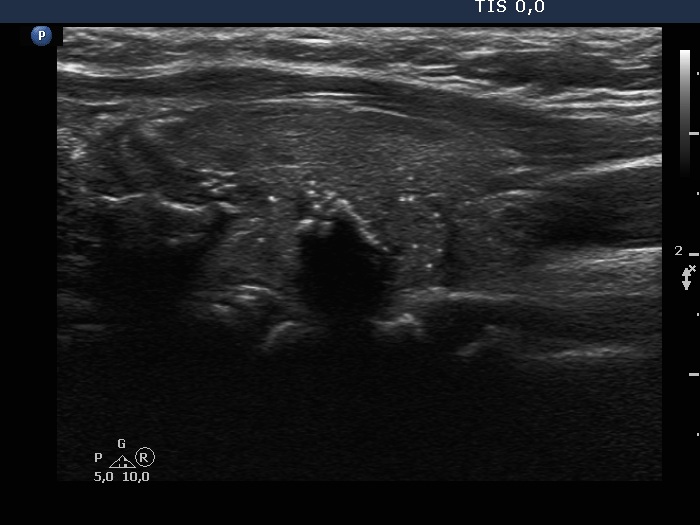

Ultrasonography. The thyroid was minimally hypoechoic and had more hypoechoic areas corresponding to the underlying thyroiditis. There was a nodule in the dorsal part of the left lobe. The nodule was a bit brighter compared to the extranodular tissue but darker compared to a healthy thyroid. Beside macrocalcification, the nodule contained numerous microcalcifications. The latter occurred even outside the tumor. The borders of the nodule were difficult to judge. The lesion presented a combined perinodular and intranodular vascularity.

The extrathyroidal spread toward medial direction, i.e., the invasion of the trachea, is almost always impossible to judge because the cartilaginous wall of the traches hinders the evaluation of ultrasound signs of extrathyroidal extension.

Depending on the 'normal' reference tissue, the lesion can be regarded as iso/hyperechoic or minimally/moderately hypoechoic, the reference tissue is the non-nodular part of the actual patient or a healthy thyroid, respectively.

This is an example of invasive spread which is characterized by isolated microcalcifications relatively far from the primary tumor focus.